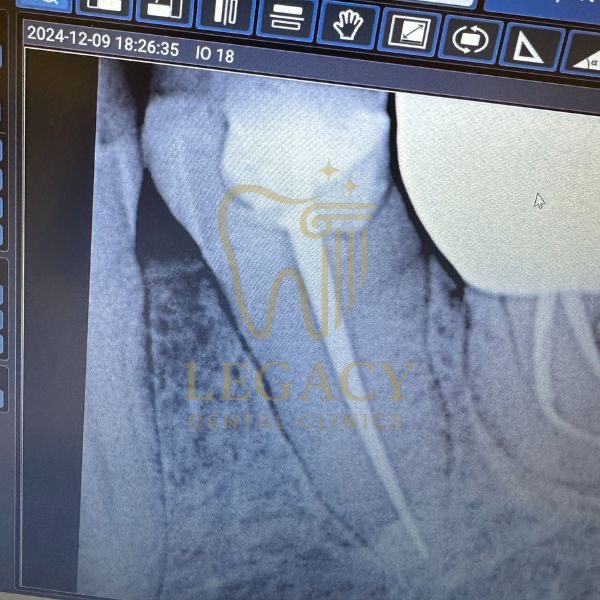

حالة زراعة فورية لسن أمامي - د.عمر نافوخ